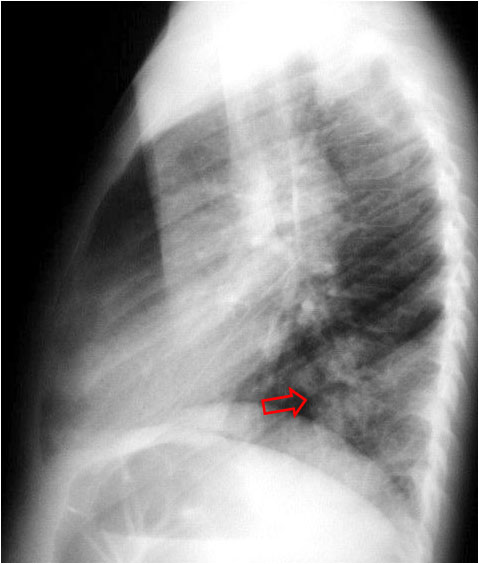

SIGNO DE LA DENSIFICACIÓN VERTEBRAL

Signo de condensación pulmonar en la radiografía lateral de tórax. En la radiografía lateral normal, la densidad de la columna torácica tiende a disminuir desde la parte superior hasta el diafragma; la alteración de ese patrón por la presencia de una densidad superpuesta a la columna (área marcada), indica la existencia de una consolidación pulmonar. Este signo adquiere especial valor cuando en la proyección posteroanterior la consolidación está oculta en el espacio retrocardíaco o en la base pulmonar.